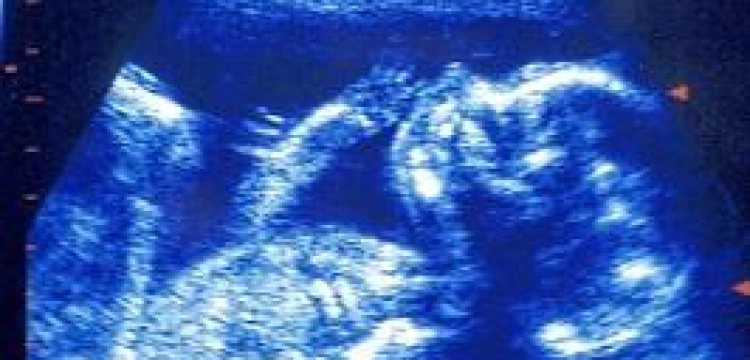

"Daily Telegraph" podaje, że film zrealizowano w berlińskim szpitalu Charité w listopadzie 2011 roku. Niemieccy badacze uchwycili na nim poród dziecka 24-letniej kobiety, która zgodziła się na "pokazanie" ostatniego etapu porodu. Film powstał dzięki rezonansowi magnetycznemu i trwa zaledwie 30 seksund.

Widzimy na nim coś najbardziej niezwykłego: narodziny dziecka przez kanał rodny. Możemy też zaobserwować jak duży wysiłek towarzyszy noworodkowi w drodze na świat.

Oto filmik: